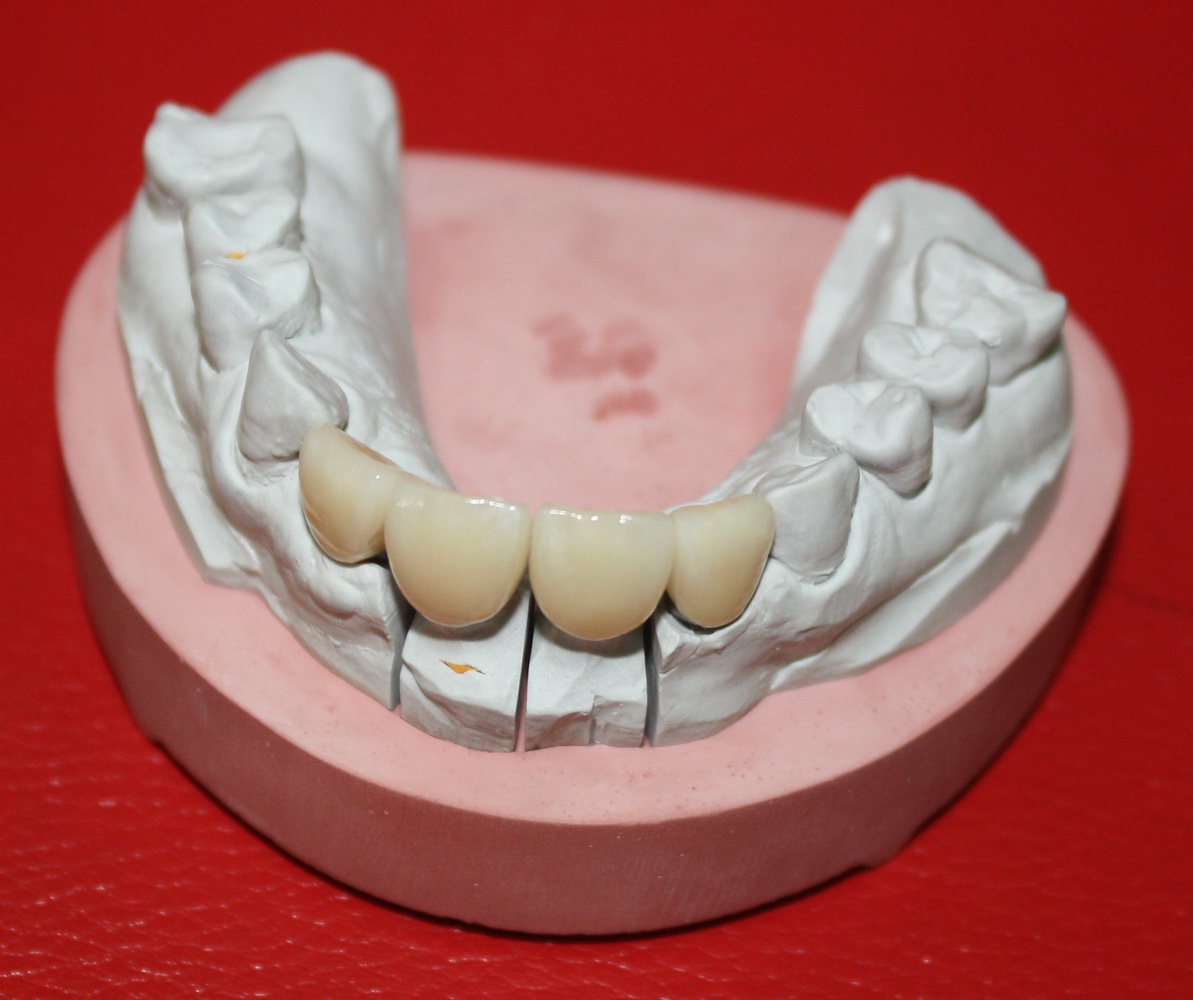

С этого момента можно перестать переживать — десневой контур сформировался правильно, мы получили достаточный объём и качество окружающей платформу имплантата десны. Можно приступать к изготовлению постоянной протетики. Подрядчиком стала зуботехническая лаборатория French Creative, одна из топовых лабораторий Москвы.

На первом этапе зафиксировали и индивидуализировали трансферы, с помощь которых положение имплантатов переносится в гипсовую модель:

затем сняли оттиски и передали из в зуботехническую лабораторию. Кстати, на этом этапе мы также рекомендуем делать прицельные снимки для контроля посадки трансферов.

Процесс изготовления постоянных коронок состоит из нескольких этапов, а все лабораторно-клинические работы занимают 1-2 недели.

Сначала диоксида циркония изготавливаются индивидуальные абатменты, передаются в клинику для примерки и коррекции:

Следом идут керамические коронки, для которых предварительно выбирают цвет и фактуру: